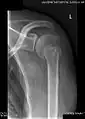

X-ray at left shows anterior dislocation in a young man after trying to get up from his bed. X-ray at right shows same shoulder after reduction and internal rotation, revealing both a bony Bankart lesion and a Hill-Sachs lesion.